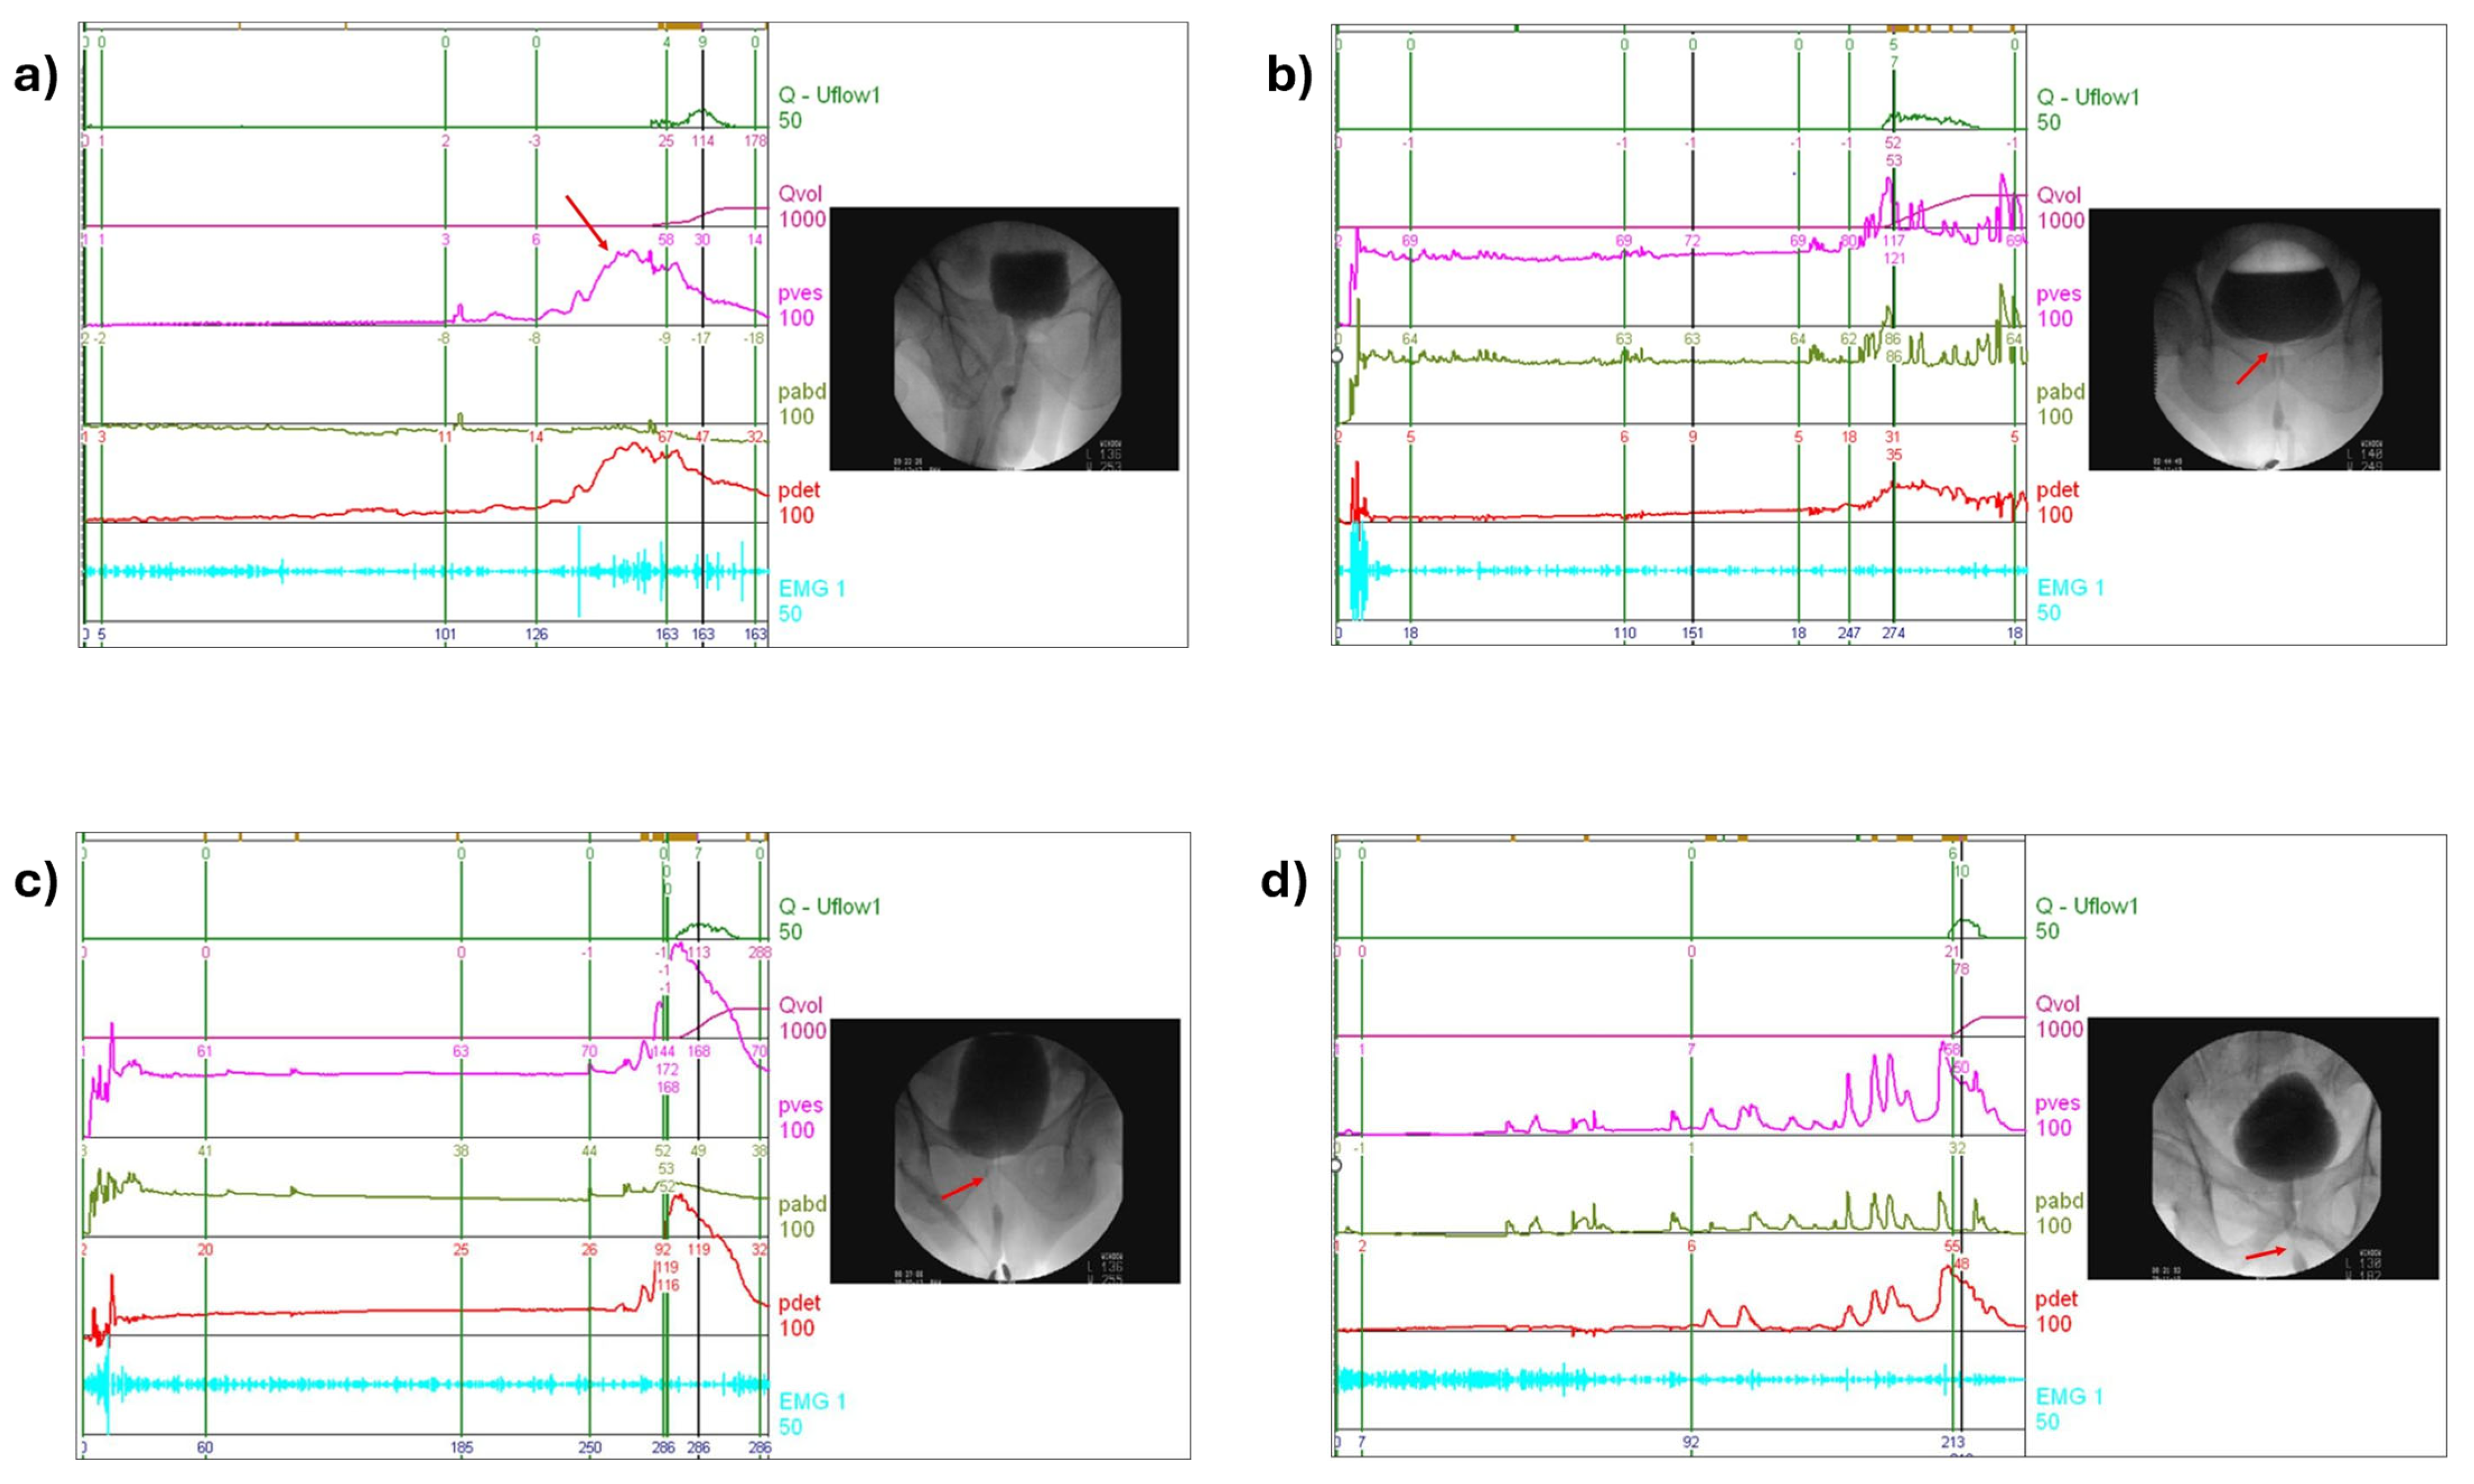

2.2. Noninvasive Assessment Variables and VUDS

2.3. Definition of the Prediction Targets